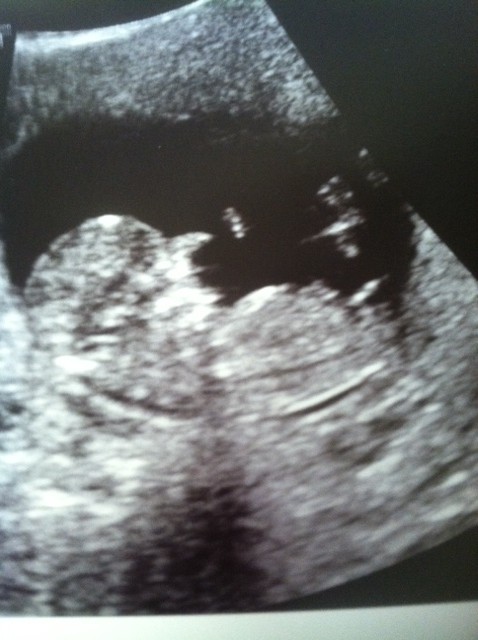

I wanted to add one more pic in case it showed any gender clues. Thanks for all of the guesses!

I think I'm officially nubcessing! So I've drawn lines and I wanted to see if anybody thought that baby's spine is curled making it look more boyish? I'm totally grasping for straws here. If my lines are off then tell me that too. I sort of guessed at where baby's spine is on the first 2 because I couldn't really tell. I'm really wishing that I had waited a few days for the NT scan. It probably would have been more obvious later in the week! Telling me to step away from the computer and chill out is also an appropriate answer :oops: